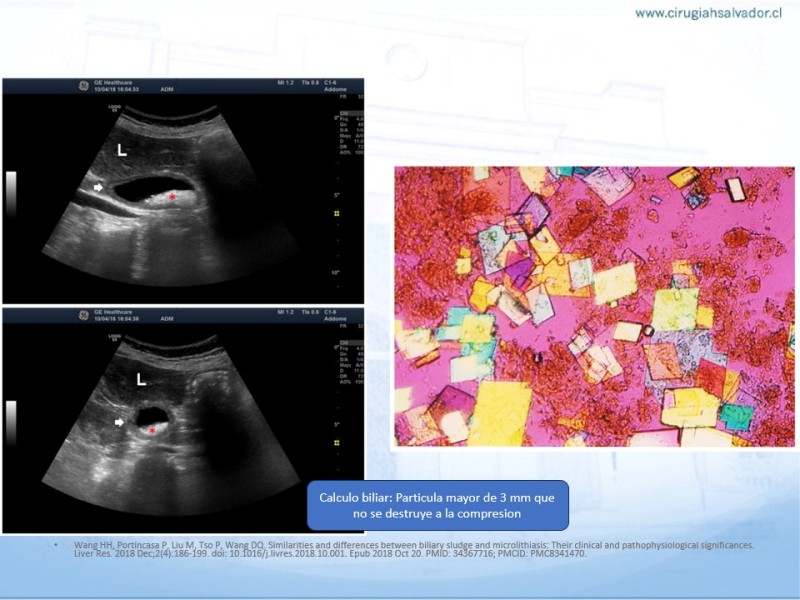

Barro Biliar